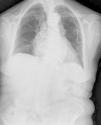

Paciente 1Mujer de 75 años de edad portadora de un marcapasos definitivo unicameral por una fibrilación auricular con respuesta ventricular lenta. Se realizó un primer implante en región prepectoral izquierda, y por úlcera de decúbito del generador y trombosis venosa a los 12 años se cambió al lado derecho. Trascurridos 2 años presentó de nuevo una úlcera, por lo que se decidió implante del marcapasos por vía femoral (fig. 1). La paciente hasta la actualidad no ha presentado ninguna complicación, incluyendo infecciones o dislocaciones del electrodo. A los 5 años, aproximadamente, precisó el recambio del generador por encontrarse en tiempo de reemplazo electivo implantándose en el mismo bolsillo.

En nuestros pacientes el abordaje se llevó a cabo mediante una modificación de la técnica3 descrita originariamente por Ellestad et al.2, alojando el generador en una bolsa realizada por debajo del ligamento inguinal (fig. 2). Aunque a priori, es fácil pensar que esta localización podría limitar la movilidad y suponer cierta incomodidad, en todos los casos ha sido bien tolerada sin molestias en la marcha ni en el bolsillo.